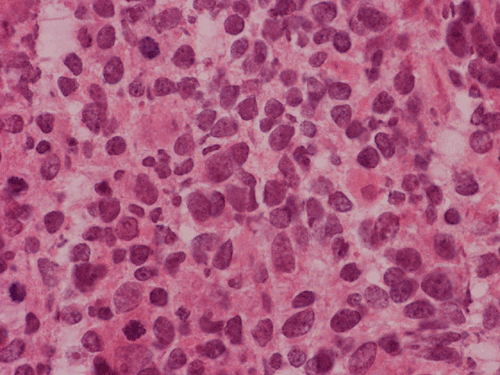

The volume of tissue received for examination amount to an aggregate of 4.0 x 2.0 x 1.5 cm in combined size. Grossly, the tissue is soft and has a creamy color with hemorrhage. The intraoperative cytologic preparation demonstrate a neoplasm composed with small to medium sized blue cells that smear out rather homgeneously and evenly. If you pay attention, there are some larger cells with a substantial amount of cytoplasm even at low magnification (Panel A). On high magnification, the nuclei are rather uniformly large, with high grade of pleomorphism, and almost all cells contain a distinct nucleoli. Apoptotic bodies and mitoses are frequent (Panel B). There are also large cells with prominent nucleoli and substantial amount of eosinophilic cytoplasm. These cells are suggestive of rhabdoid cells but none of them have the distinct inclusion body like cytoplasmic eosinophilic body of the rhabodid cells in atypical teratoid rhabodid tumor (Panel C). In the frozen section, both small to medium sized cells and cells with large nuclei with large, prominent, and eosinophilic nucleoli (Panel D and E). In the permanent sections, there is extensive necrosis (Panel F). The histology is in general agreement with that of frozen section except that the tumor cells appear to have more cytoplasm and more plemorphic, large nuclei with prominent nucleoli in comparison to the frozen section (Panel G). Large cells with substantial volume of cytoplasm, large, bizarre nucleoli and prominent, eosinophilic nucleoli are also noted (Panel H). There is a generalized degree of high grade pleomorphism. Results of immunohistochemistry are as follow:

Comment: This is an interesting case. Histologically, the overall morphology is consistent with a medulloblastoma with high grade of pleomorphism. Therefore, a diagnosis of large cell (anaplastic) medulloblastoma is the most likely diagnosis. The problem is the large cells with substantial amount of cytoplasm and large bizarre, eccentric nuclei with large nucleoli. These features raise the possibility of an atypical teratoid rhabdoid tumor (ATRT). These cells, if you observe carefully, lack the cytoplasmic, eosinophilic, inclusion body typical for rhabdoid cells. Nuclear wrapping is not readily seen. In fact, we did not find unmistakable nuclear wrapping until we looked at the immunohistochemistry for neurofilament. There are three immunohistochemical features in this case that are against a diagnosis of ATRT. First, vimentin is typically positive in most, if not all, tumor cells particularly those cells with rhabdoid changes. Second, most ATRT are positive for EMA. Third, the most powerful proof is the positive immunoreactivity of BAF47 which would be negative in ATRT. The negative result for desmin is helpful in ruling out the possibility of a rhabdomyosarcoma.

Large cell and anaplastic medulloblastomas are recognized as different variants in the new WHO classficiation 1. They share many basic features with medulloblastoma 2, 3. The most notable differences are large cell size, increased variation of nuclear size, prominent and even eosinophilic nucleoli, increased mitotic figures and number of pyknotic or apoptotic cells, and extensive, geographic areas of necrosis. In the experience of the authors, most of the tumor cells in large cell and anaplastic medulloblastomas have high nuclear to cytoplasmic ratio in a manner similar to that of the classic variant. As per the new WHO classification, large cell medulloblastomas are composed mainly of large cells with more cytoplasm than the classic variant or the anaplastic variant. In the experience of the authors, this distinction is not always possible. The case being illustrated here includes some large cells with substantial amount of cytoplasm and but these cells only represent a portion of the tumor cell population. In general, anaplastic and large cell medulloblastomas have less favorable prognosis than the classic variant of medulloblastoma. However anaplastic changes are uncommon and does not affect the prognosis in adult cases as per one study 4.